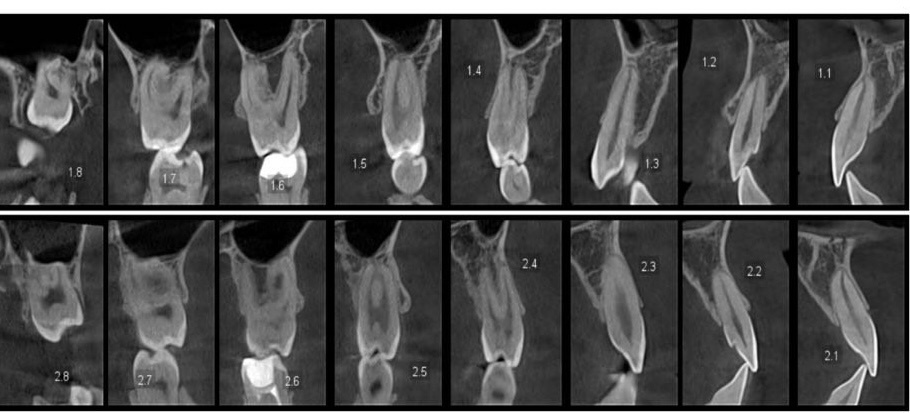

• КЛКТ челюстей

В плане должно быть указано: какие исследования проведены, что они показали, какие проблемы выявлены.

Да. Для взрослых стандарт — КЛКТ челюстей. Без снимков невозможно увидеть состояние корней, объём костной ткани, скрытые воспаления. Риск — повреждение корней и неточный план лечения.